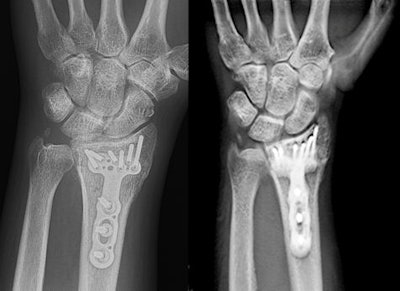

The wrist presents a tricky target for plain x-ray, however. The multiple bones in the wrist can overlap, making it difficult to view pathology on 2D radiographs. And metal implants that are increasingly being used to help the healing process can also create problems.

Ha's team decided to compare tomosynthesis to radiography in patients being treated for wrist fractures at the university. Patients received both tomo and conventional radiography within one year of hardware placement, with the tomosynthesis system acquiring 60 slices. Noncontrast CT scans were also acquired to create a gold standard for comparison.

The researchers evaluated a total of 49 patients (31 men, mean age of 47 years) with a total of 51 bones with implanted hardware. The most common indications were distal radius fracture (43%), scaphoid fracture (18%), and metacarpal fracture (18%), and fracture lines were analyzed for four cortices -- medial, lateral, anterior, and posterior.